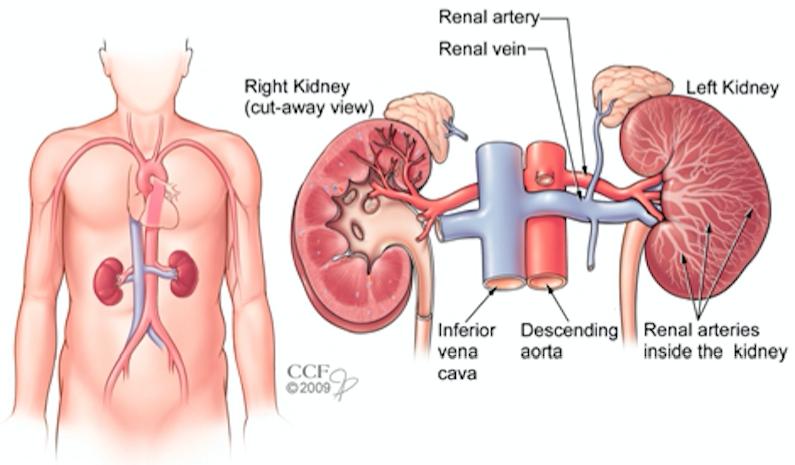

肾脏位于脊柱两侧,左右各一。肾脏在尿液的产生中发挥着重要作用,这个过程中肾脏可以排除血液中的废物,保留对人体有用的营养物质,是参与身体新陈代谢的重要器官。

肾脏的形态像一颗蚕豆,内侧呈袋状向内凹,像一个钱包,称为肾窦(Renal sinus)。肾实质包绕肾窦,超声上显示肾实质光点亮度较低,肾窦光点亮度明显增高,位于中央呈椭圆形,内包括肾盂(Renal pelvis)、肾盏(Renal calyx)、血管等。肾盂、肾盏与输尿管(Ureter)相通。